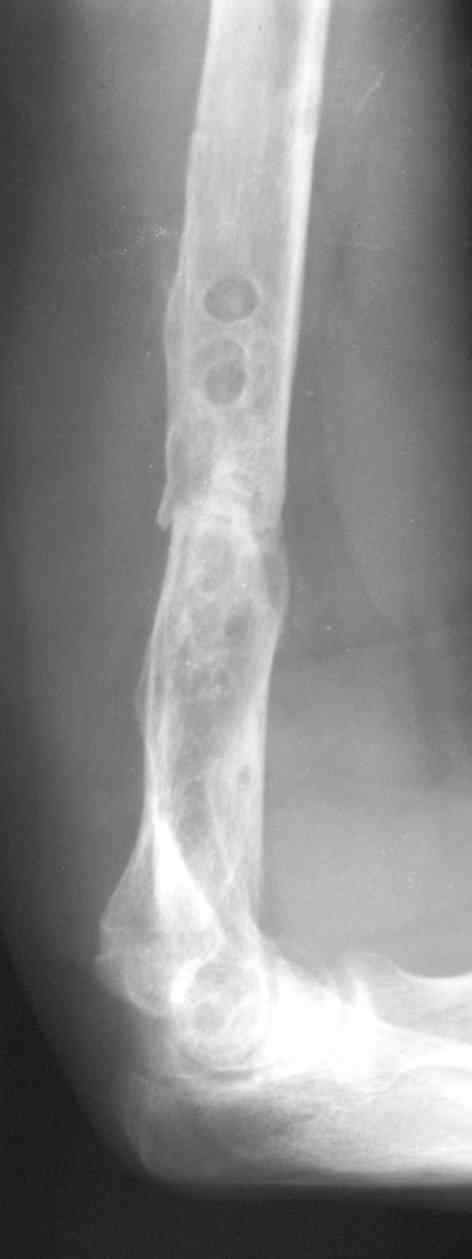

На примере два случая, извиняюсь за качество снимков, снимки и случаи из бывшего союза.

Первая больная с "успехом" была прооперирована 6 раз различными методами открытого и закрытого

остеосинтеза, включая то, что в Кисловодске заезжим австралийским "кудесником" на ложный сустав уложена скорлупа от страусиновых яиц. Последняя операция одиноким локинг плейт в одной из клиник.

Через год по поводу тех же проблем сделали ревизию, оригинальную пластину оставили как есть, только укрепили добавлением еще одной пластины и сделали костную пластику.

Через два месяца увидели признаки консолидации.

Второй случай, также после множественных операций:

пластина, аппарат, серкляж и парез нерва.

Также ревизия, из-за низкого состояния доступ был

сделан через остеотомию локтевого отростка.

Ложный сустав фиксирован двумя локинг плейт с

аутокостной пластикой, также через два месяца увидели признаки консолидации.

Движение в суставе разрешили в две недели.